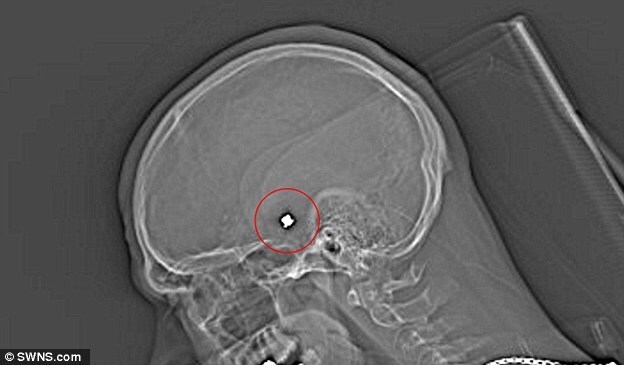

Ben Smit, un uomo di 28 anni padre di due figli, è miracolosamente riuscito a sopravvivere dopo essere stato colpito alla testa da un colpo di arma da fuoco: l'uomo, tuttavia, vive con una vera e propria "bomba a orologeria" nel cranio visto che un proiettile è rimasto conficcato nel cervello e un suo spostamento anche di pochi millimetri potrebbe causarne il decesso oppure danni permanenti.

L'uomo è stato vittima di un banale incidente: era infatti a caccia insieme quando un amico, per gioco, gli ha puntato il fucile contro ed ha premuto il grilletto credendo che non ci fossero proiettili in canna. In realtà, invece, c'erano dei pallini per la caccia al coniglio che hanno sfondato la scatola cranica di Ben e si sono conficcati nel suo cervello. Trasportato in ospedale ancora vivo, benché in gravi condizioni, i medici hanno effettuato tutti gli esami necessari prima di capire che non avrebbero mai potuto estrarre le pallottole. L'uomo è rimasto ricoverato in stato vegetativo per nove mesi, quindi si è svegliato e qualche mese fa, dopo una complessa riabilitazione, è persino tornato a lavorare. I dottori sono però stati chiari: la sua vita è appesa a un filo e potrebbe bastare un movimento brusco perché i pallini di piombo raggiungano aree sensibili del suo cervello uccidendolo o lasciandolo per sempre cerebroleso.